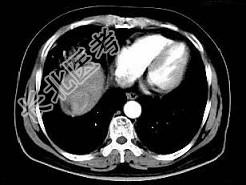

- 单项选择题根据所提供的图像,最可能的诊断是 ( )

A、肝血管瘤

B、局灶性结节增生

C、肝硬化再生结节

D、肝癌

E、肝转移癌